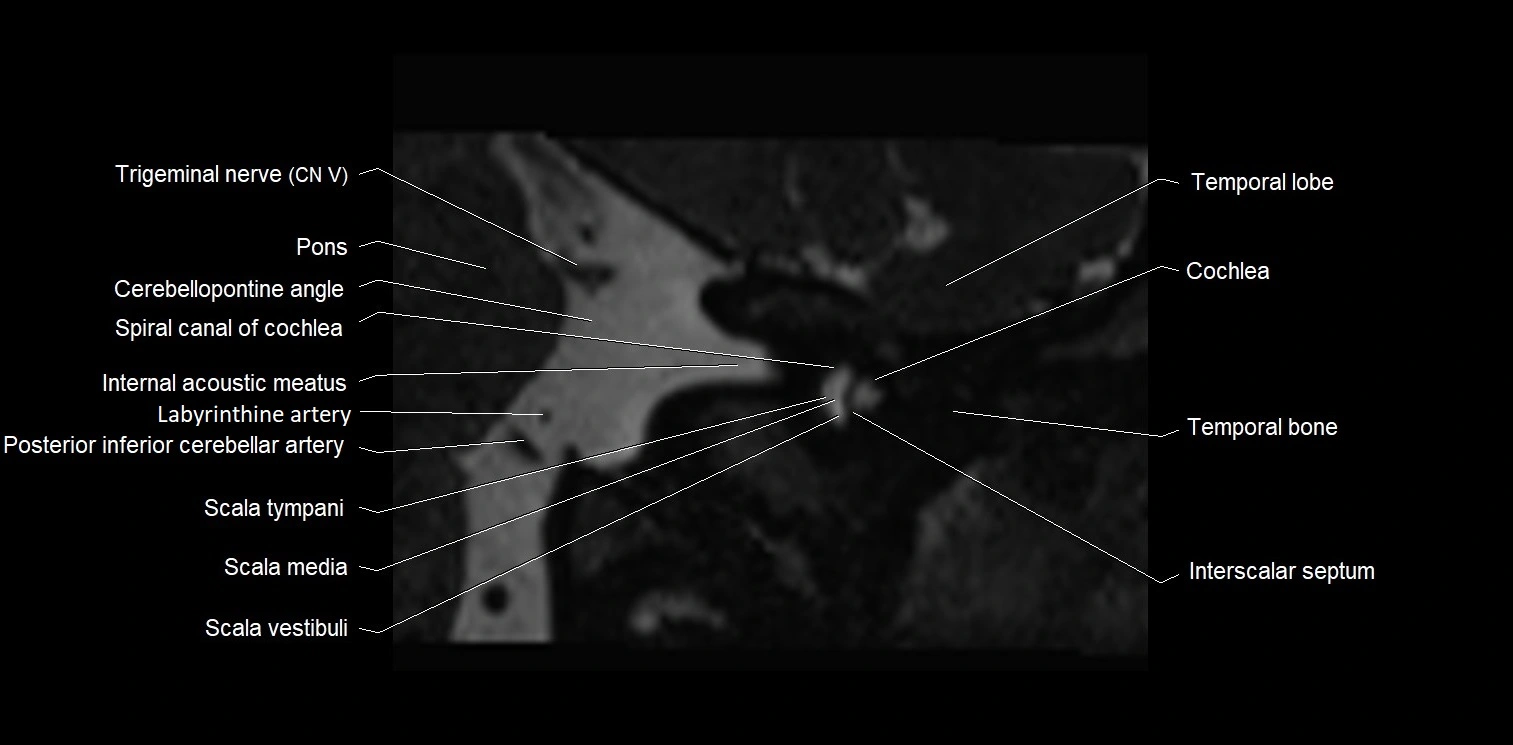

MRI Appearance

• The abducens nerve is a small, thin, linear structure

• Best visualized on high-resolution T2-weighted 3D MRI sequences (e.g., FIESTA or CISS)

• Seen as a hypointense (dark) line running from the brainstem at the pontomedullary junction, traversing the prepontine cistern, and entering Dorello’s canal under the petrosphenoidal ligament, then into the cavernous sinus, and finally the orbit

• May be challenging to visualize in standard MRI due to its small size

• Pathology may be inferred by absence, displacement, or enhancement of the nerve